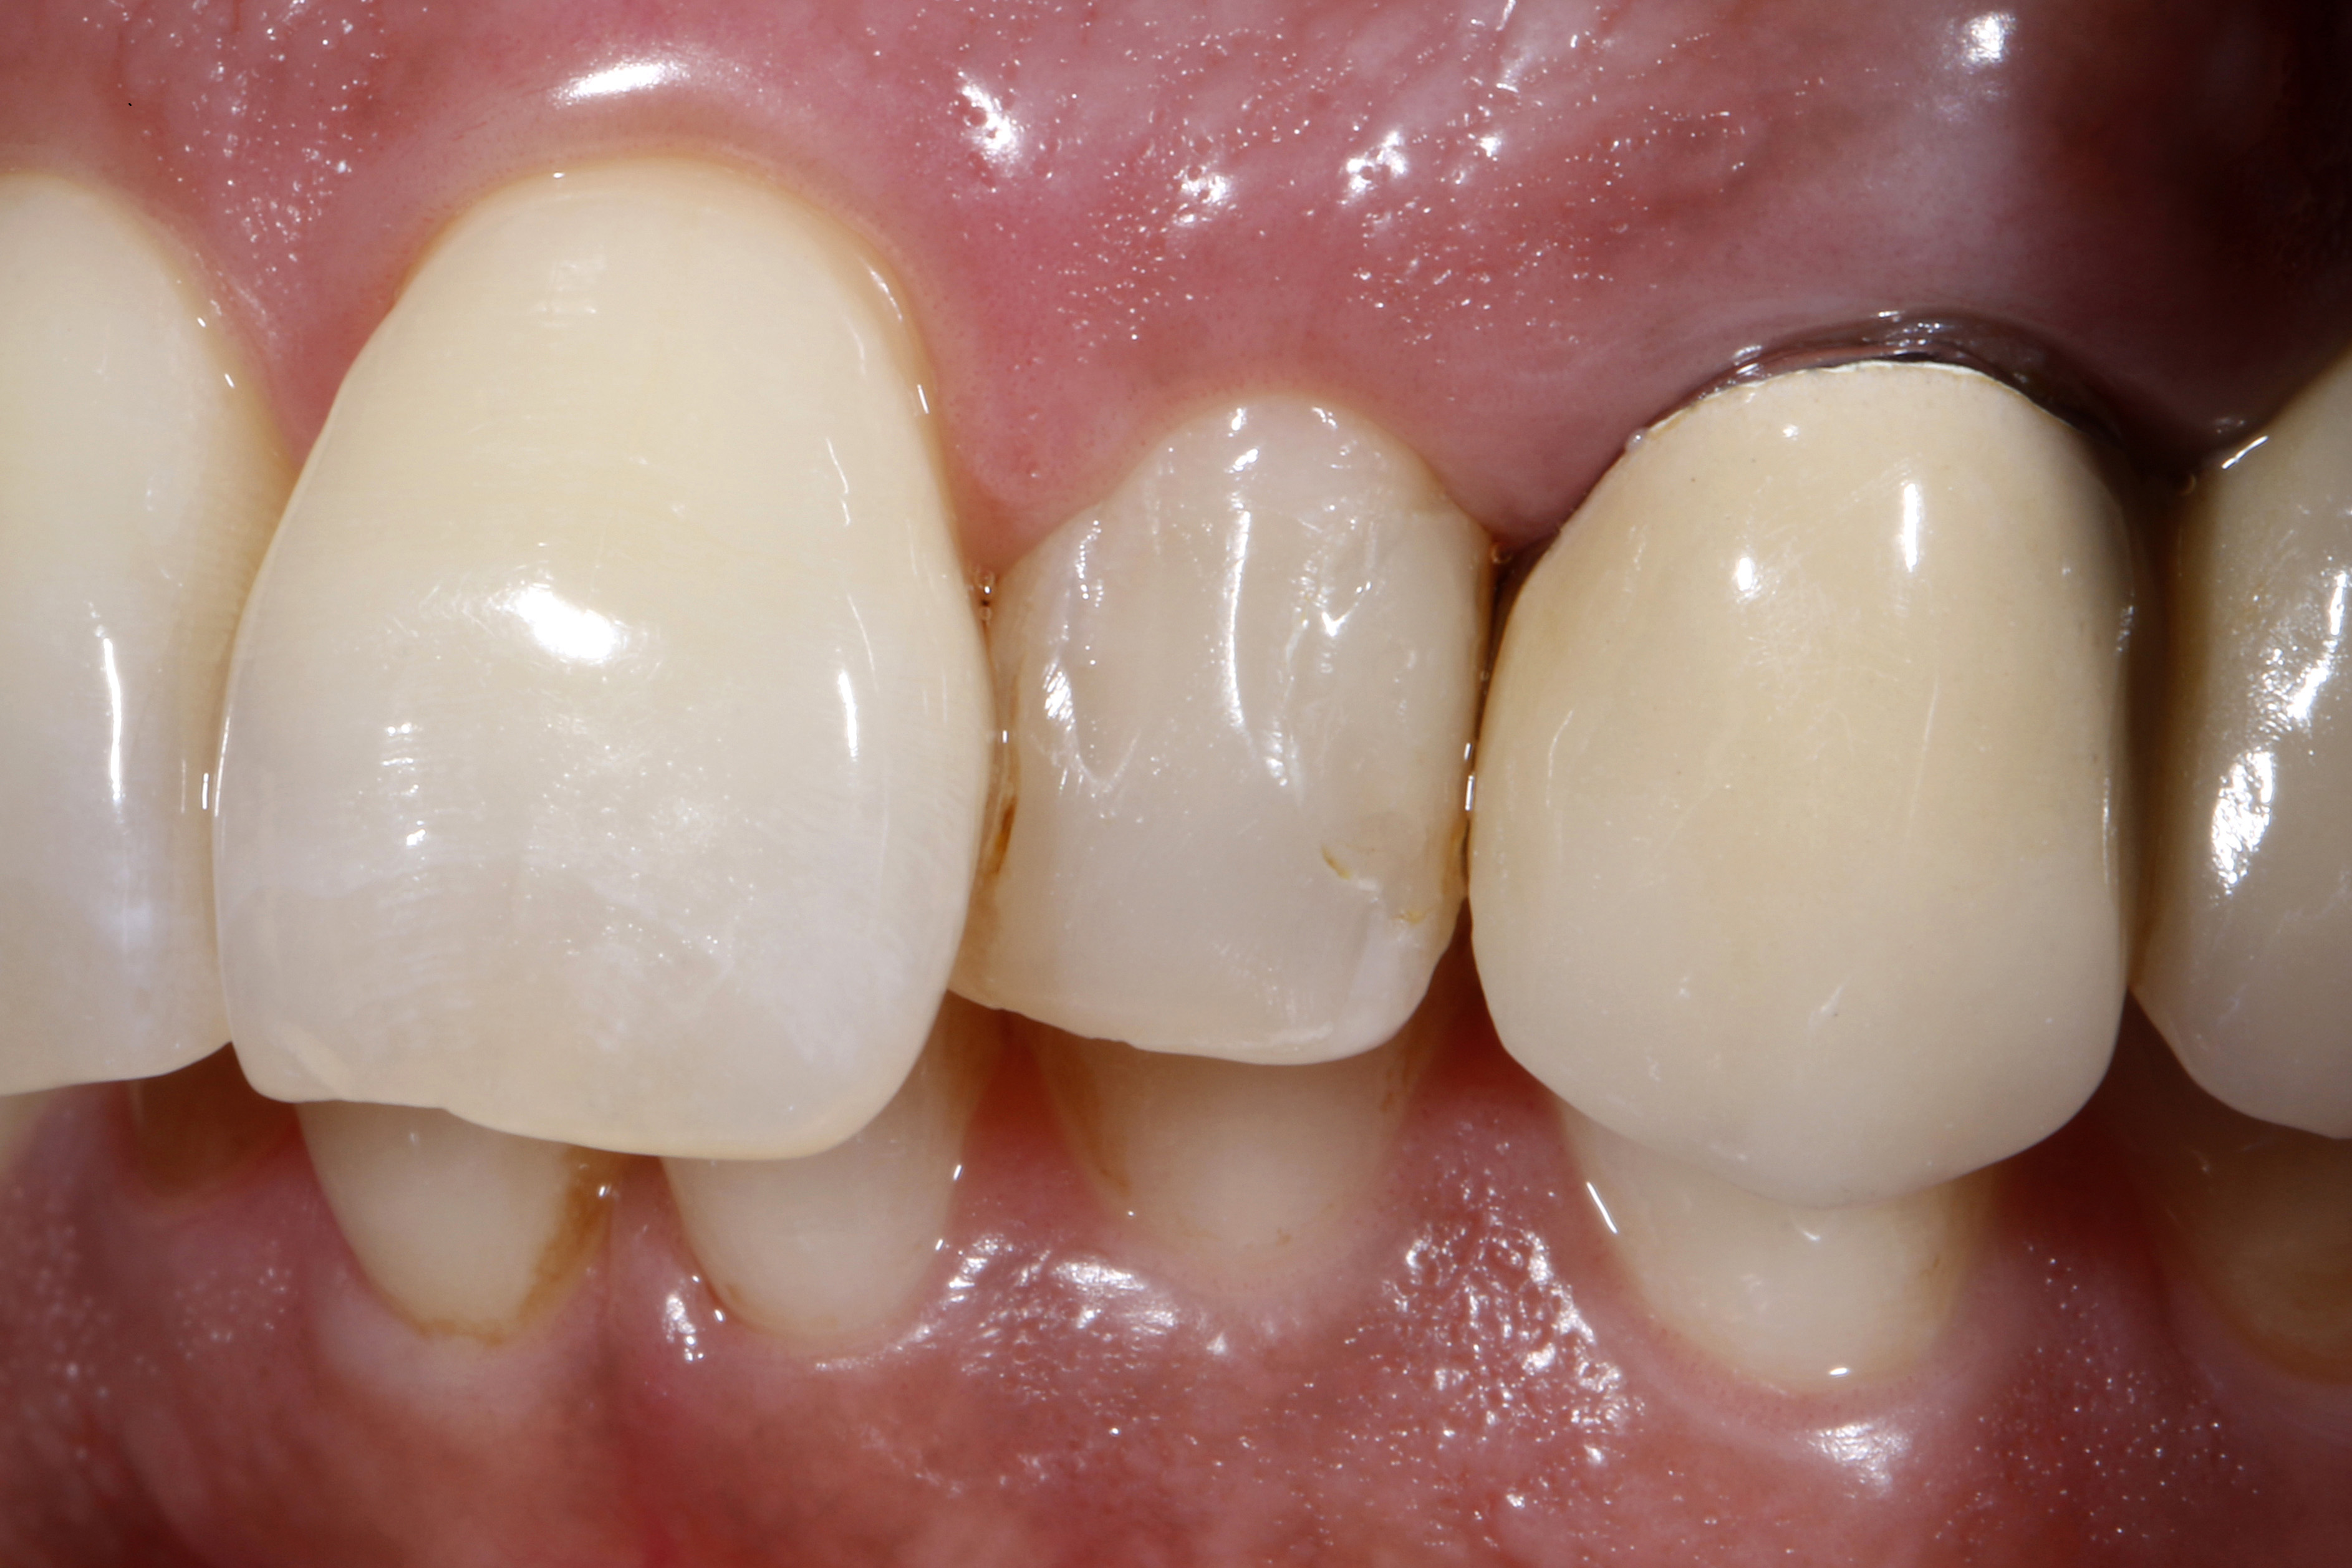

Do naszego gabinetu stomatologicznego zgłosiła się 60-letnia pacjentka z prośbą o lepsze optyczne ustawienie w łuku zębowym lewego bocznego siekacza szczęki, który jest wyraźnie położony podniebiennie w stosunku do lewego siekacza centralnego (ryc. 1 i 2).

Oprócz samego zęba, pacjentce szczególnie przeszkadzał fakt, że ząb wydawał się znacznie ciemniejszy w uśmiechu w porównaniu z lewym siekaczem centralnym i koroną PFM na lewym kle. Ząb bezzwłocznie zareagował nadwrażliwością na test na zimno, nie wykazał przy tym nieprawidłowości w teście opukiwania. Po zapoznaniu się z możliwymi alternatywami leczenia i ich kosztami, pacjentka zdecydowała się na licówkę bezpośrednią z użyciem uniwersalnego kompozytu GrandioSO Unlimited (VOCO GmbH, Cuxhaven).

Ryc. 1, 2. Sytuacja wyjściowa: lewy siekacz boczny jest ustawiony wyraźnie podniebiennie w stosunku do zębów sąsiednich. To przeszkadza pacjentce, który chciałaby uzyskać lepszą integrację wizualną z łukiem zębowym.